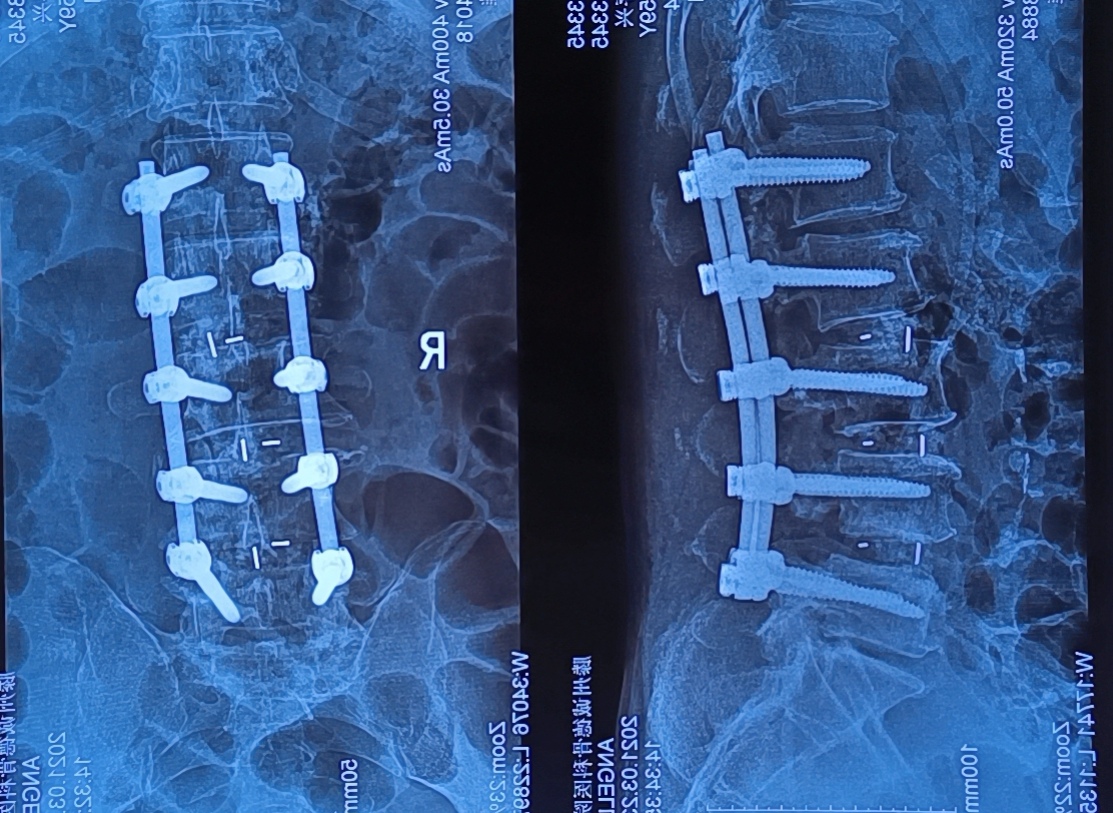

然而、萬幸的是在2020年11月21日,患者來到了滕州誠德骨科醫(yī)院就診,經(jīng)專家查體,確診為腰椎管狹窄癥。與患者溝通后做了腰1-腰5減壓植骨內(nèi)固定術(shù),術(shù)后患者癥狀立刻減輕,術(shù)后第三天就可以下地行走。